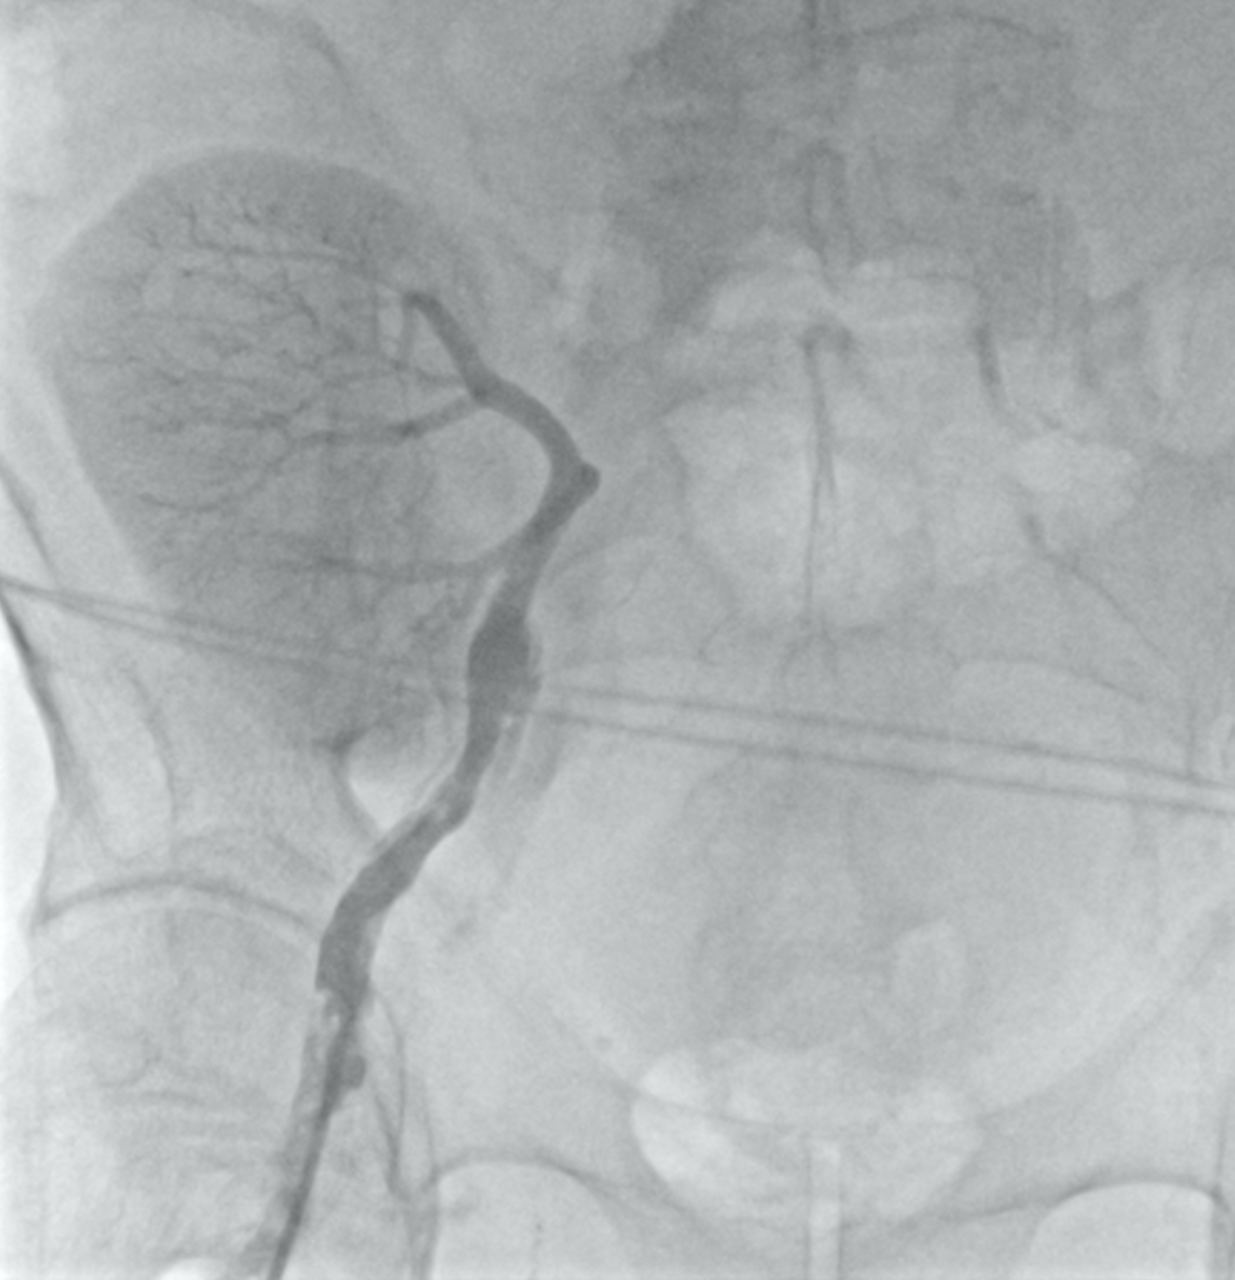

Под местной анестезией пунктирована правая бедренная артерия, установлен интродьюсер. Выполнена ретроградная ангиография правой бедренной артерии: выявлена хроническая окклюзия наружной подвздошной артерии, ниже окклюзии была визуализирована артерия транспланта почки (рис. 1).

Рисунок 1. Ретроградная ангиография бедренной артерии справа с контрастированием почечного трансплантата.

Выявлена окклюзия наружной подвздошной артерии.